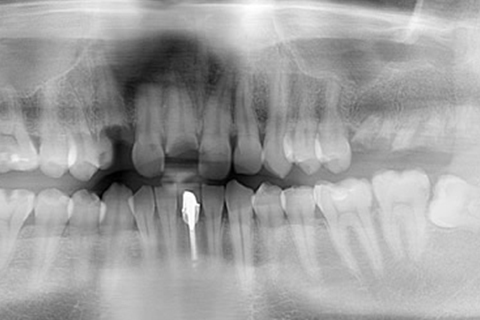

症例2

- 年齢・性別

- 57歳男性

- 治療期間

- 3ヶ月

- 抜歯

- なし

- 治療費

- 165万円

- 備考

- 左上5.6.7 及び左下6.7欠損

- 治療内容

- 左上5.6.7と左下6.7欠損部にインプラント埋入

- 施術の副作用(リスク)

- オペによる知覚障害。インプラントによる歯肉炎。インプラント脱落。